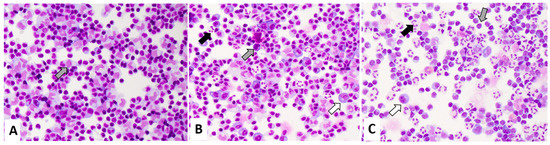

The cytomorphological evaluation of CSF immune cells was performed from GIEMSA-stained cytospin preparations by an experienced team of neurologists. Routinely, the presence of CSF immune cells (i.e., lymphocytes, monocytes, their activation states, presence of granulocytes and plasma cells) is semi-quantitatively categorized as few, several, or abundant. Cell types not mentioned (i.e., granulocytes, plasma cells in an inflammatory setting) are classified as not present. The semi-quantitative presence of neutrophilic granulocytes is further assessed in relation to mononuclear cells (i.e., lymphocytes and monocytes) and categorized as few granulocytes (fewer neutrophilic granulocytes than mononuclear cells), several granulocytes (more than a few neutrophilic granulocytes, with approximately comparable numbers of neutrophilic granulocytes and mononuclear cells), and abundant granulocytes (more neutrophilic granulocytes than mononuclear cells). For this study, we also included the category “no granulocytes”. Similarly, the presence of plasma cells was dichotomized into no plasma cells and plasma cells. An example of the cytological CSF classification is shown in Figure 1.

Figure 1. Exemplary May Grunwald Giemsa stainings of definite Lyme neuroborreliosis. The samples show activated mononuclear cells (grey arrow) and plasma cells (white arrow). The semi quantitative classification of granulocytes (black arrow) is displayed: (A) “no granulocytes” (B) “few granulocytes” (C) “several granulocytes”.